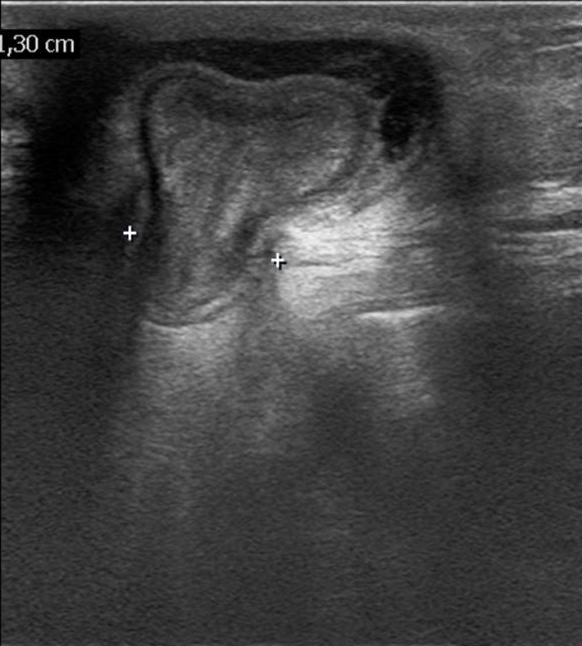

• A knife falling from a kitchen table stuck into the right thigh of an 18 year old young man. Increased femoral circumference and pulsating mass were seen. In the upper image with femoral Duplex sonography pseudoaneurysm of the femoral artery is detected

In the middle with a CT angiography the pseudoaneurysm shows contrast enhancement.

In the lower image 3D reconstruction of the CTA

11. A knife falling from a kitchen table stuck into the right thigh of an 18 year old young man. Increased femoral circumference and pulsating mass are seen. In the upper image with femoral Duplex sonography pseudoaneurysm of the femoral artery is detected In the middle with a CT angiography the pseudoaneurysm shows contrast enhancement. In the lower image 3D reconstruction of the CTA